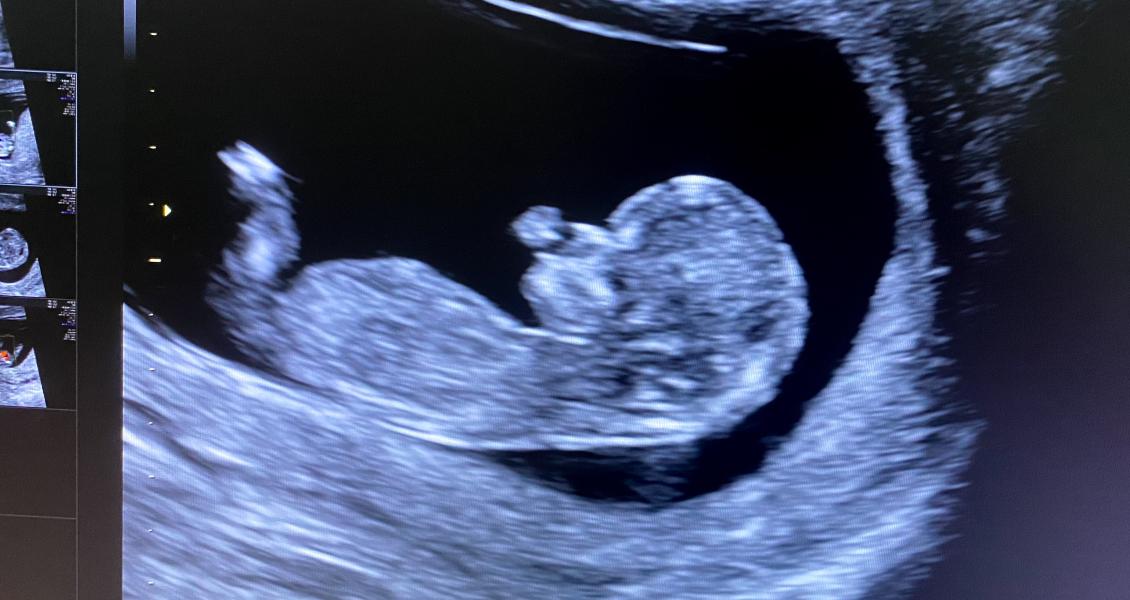

Первый скрининг пройден🥰 По узи все хорошо, ждём результаты по крови😊